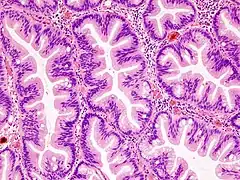

Gastrointestinal System